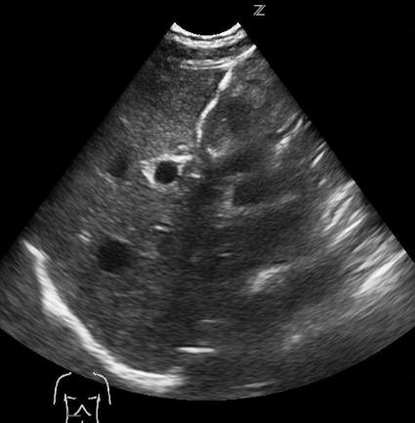

Most deep neural networks (DNNs) based ultrasound (US) medical image analysis models use pretrained backbones (e.g., ImageNet) for better model generalization. However, the domain gap between natural and medical images causes an inevitable performance bottleneck. To alleviate this problem, an US dataset named US-4 is constructed for direct pretraining on the same domain. It contains over 23,000 images from four US video sub-datasets. To learn robust features from US-4, we propose an US semi-supervised contrastive learning method, named USCL, for pretraining. In order to avoid high similarities between negative pairs as well as mine abundant visual features from limited US videos, USCL adopts a sample pair generation method to enrich the feature involved in a single step of contrastive optimization. Extensive experiments on several downstream tasks show the superiority of USCL pretraining against ImageNet pretraining and other state-of-the-art (SOTA) pretraining approaches. In particular, USCL pretrained backbone achieves fine-tuning accuracy of over 94% on POCUS dataset, which is 10% higher than 84% of the ImageNet pretrained model. The source codes of this work are available at https://github.com/983632847/USCL.